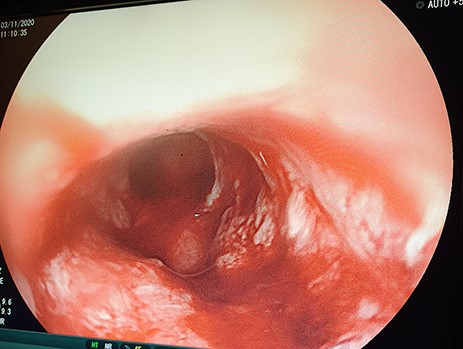

A 46-year-old female presented with progressive grade-six dysphagia, vomiting and significant unintentional weight loss. She was wasted and had a BP of 82/53 mmHg, pulse rate of 80 beats per minute, temperature of 36.4°C, saturating at 98% on room air. Her full blood picture was normal with haemoglobin of 12.3 g/dl, Creatinine 41 μmol/l, and urea was <1.0 mmol/l, sodium was 128.2 mmol/l, potassium 3.07 mmol/l. Chest X-ray was normal and the abdominal ultrasound showed no features of intra-abdominal metastasis. Oesophago-gastro-duodenoscopy (OGD) revealed a fungating tumour at 20 cm with almost complete obstruction (Fig. 1) and biopsies taken revealed oesophageal well differentiated invasive squamous cell carcinoma.

OGD showing a fungating tumour at 20 cm from the upper incisors with almost complete luminal obstruction.